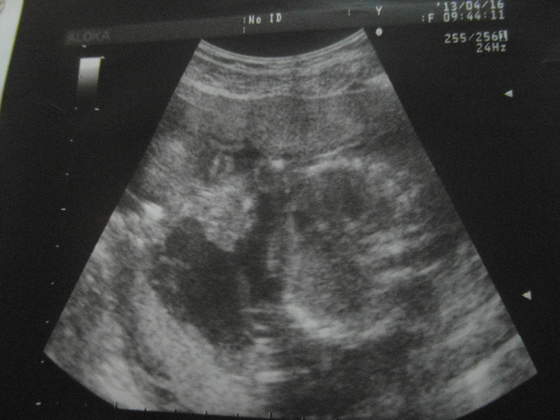

Gosheek, Madajka gratuluję zdrowych dzieciaczków. Super, że maleństwa tak pięknie się rozwijają. Dzisiaj podglądałam też na usg moje maleństwo. Wszystko ok, choć dzidziuś wstydliwy i nie lubi być podglądany. Nic między nóżkami nie wyrosło od ostatniej wizyty, także na 99,9% będzie Jagódka

Waży 236 gramów i z usg jest o tydzień większa niż z OM.